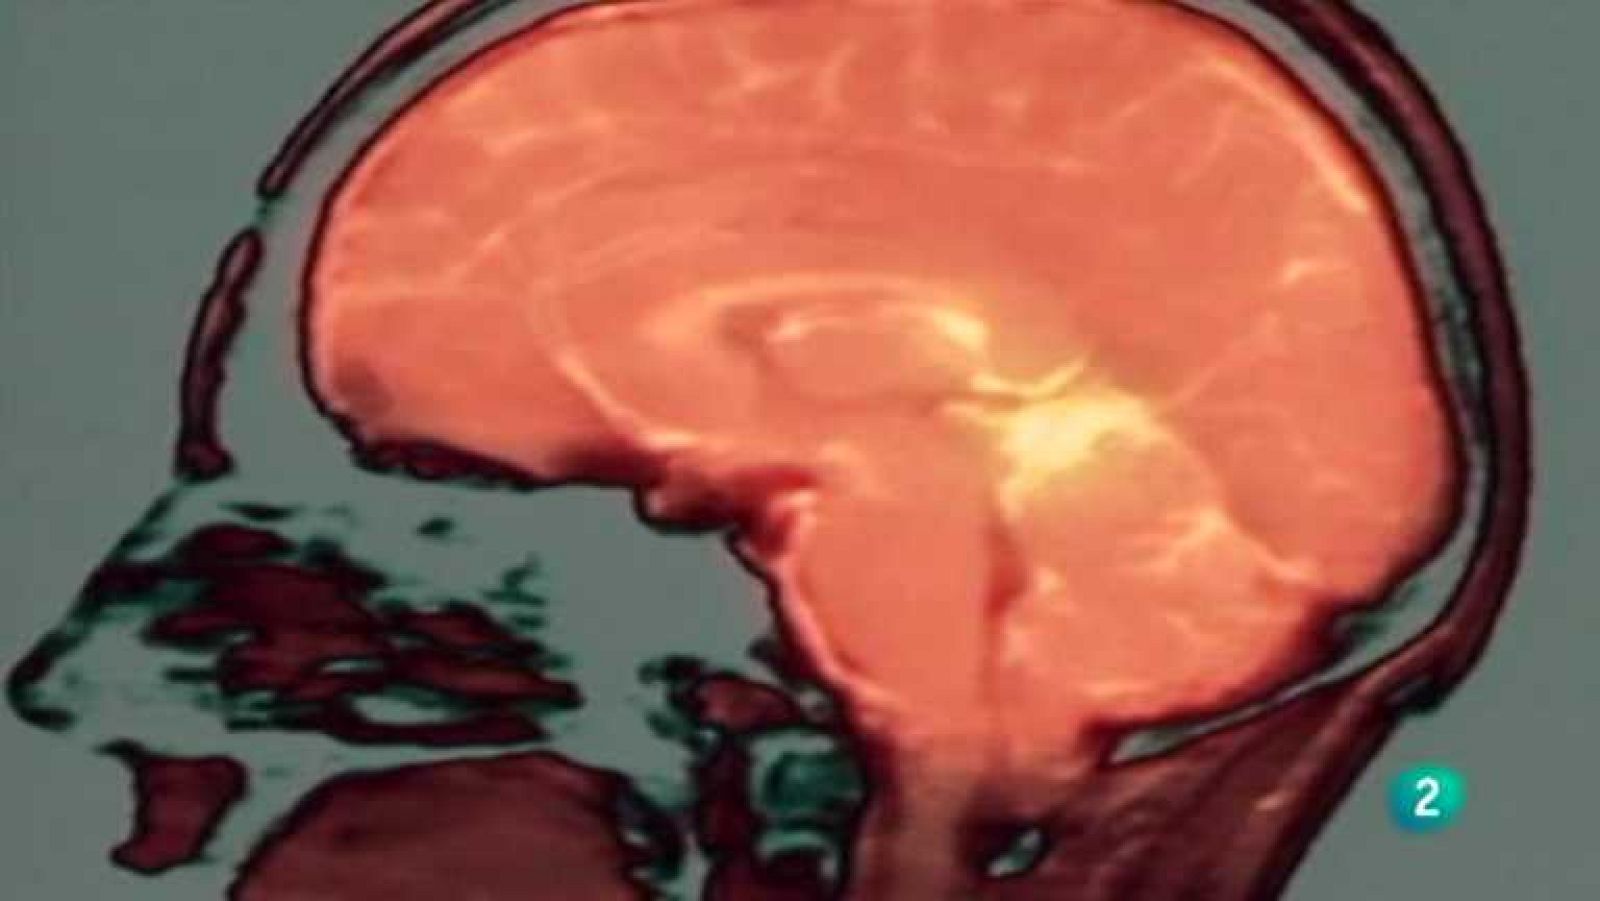

El cerebro humano tiene una notable capacidad de cambio por sí mismo. En este documental el Dr. Norman Doidge viaja a través de América del Norte...